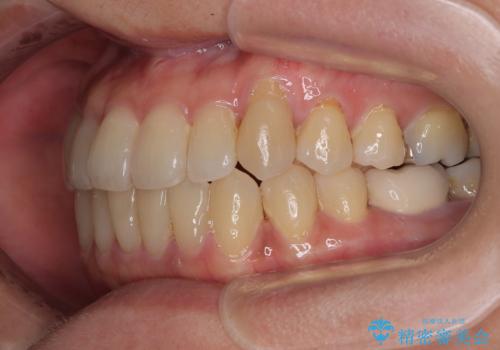

受け口と八重歯を改善 インビザライン矯正治療

受け口傾向のインビザライン矯正は比較的治療を行いやすいため、きれいに仕上げることができました。舌の突出癖が顕著であったため、改善のためのトレーニングをしっかりと行っていただきました。